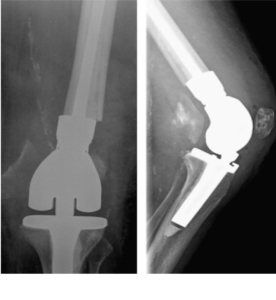

- Περιπροθετικό κάταγμα στην περιοχή του γόνατος , πολύ περιφερικό.

- Η ίδια ασθενής σε profile ακτινογραφία.

- H οστεοσύνθεση με ανάστροφη ενδομυελική ήλωση με πολύ μικρή τομή δέρματος.

- Περιπροθετικό κάταγμα λίγο πιο κεντρικά από το πέρας του εμφυτεύματος του γόνατος

- Ευθυγράμμιση του οστού και η οστεοσύνθεση με ειδική πλάκα τιτανίου και κλειδούμενους κοχλίες.

- Πολύ περιφερικό κάταγμα στο γόνατο με δύσκολη αντιμετώπιση.

- Διόρθωση του άξονα και της στροφής του οστού με πλάκα Liss μηριαίου και διαδερμική τεχνική (MIS).